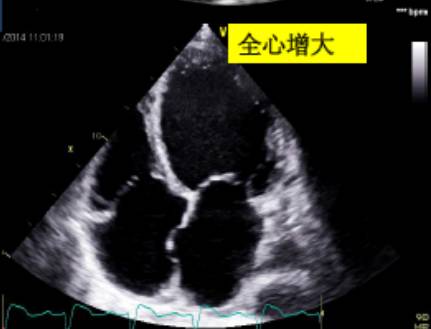

左心室正常值范围——

可用目测方法对定量数据进行反复核查。

4、右心室大小的评估

由于右心室的几何构型复杂、定量评估困难,目前临床上多采用右心室的面积或内径与左心室对比来作出定性评价。